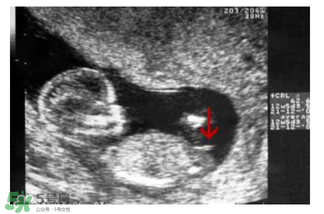

b超怎么看胎兒性別之看形狀

媽媽們可以在懷孕兩個月的時候去做B超,如果寶寶的形狀是長型的,像茄子或長條狀的,那么很有可能是男寶寶,若是橢圓或是圓型,那么可能是女寶寶。